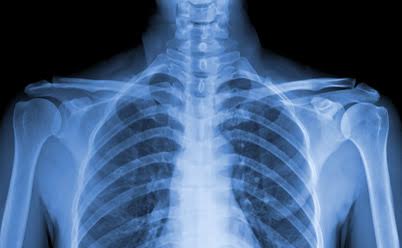

Rayos X

También llamada radiografía, es un medio de diagnóstico utilizado en la medicina. Se utiliza también para descubrir defectos en tuberías y piezas mecánicas.